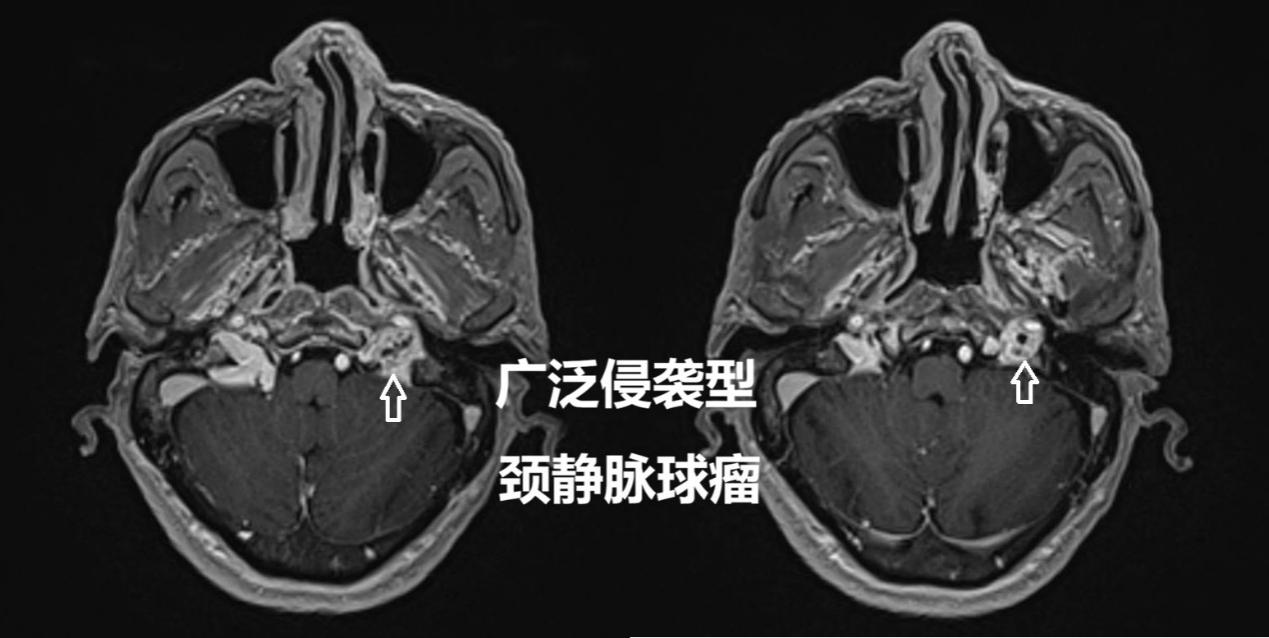

66岁的林大爷在一年前突然出现左侧颈部牵扯性疼痛,并伴有头晕、头痛和眼睛胀痛。起初他以为只是劳累或休息不足,但症状持续未见缓解。随着时间推移,他还逐渐出现了吞咽呛咳、声音嘶哑等表现,严重时食物甚至会反流至鼻腔。林大爷在家人陪同下辗转于多家医院,接受了十余项检查,却始终未能得到诊治。最终,他来到我院就诊,经过头颅磁共振(MRI)、增强CT等系统检查,林大爷被确诊为颈静脉球瘤——一种发生于颅底深处的罕见血管性肿瘤。

“颈静脉球瘤起源于颈静脉孔区的副神经节组织,虽然是良性肿瘤,但位置太特殊了——深深埋在颅底,周围全是颈内动脉、多条颅神经这些‘生命要害’,就像一颗藏在神经血管网络里的‘定时炸弹’。”接诊的神经外科刘劲松副主任医师解释道。这类肿瘤特别罕见,每百万人才有0.8到1.8例,40-60岁更容易患病。更棘手的是,它的血管极其丰富,手术切除难度极大,风险极高。稍不注意就可能引发面瘫、彻底失聪、脑脊液漏等严重后遗症,复发率也不低。

“对于这种位置复杂、手术风险高的广泛侵袭型颈静脉球瘤,放疗早就不是‘没法手术才用’的备选方案,而是越来越核心的精准治疗手段。”放疗科罗杨坤副主任医师补充道。手术治疗颈静脉球瘤,并发症发生率一直偏高,一旦出现后组颅神经功能障碍、面神经麻痹等问题,会严重影响患者的日常生活。而现代放疗技术,能精准锁定肿瘤位置,把高能射线集中对准肿瘤组织“精准打击”,既能摧毁肿瘤细胞,又能最大程度保护周围的正常神经和血管,大大降低了治疗风险。